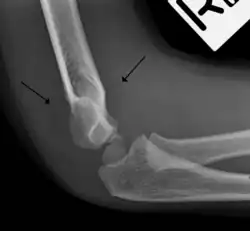

Fat pad sign: Ventral fat pad bowed and dorsal fat pad visible in a case of a nondisplaced fracture of the radius head which is not visible directly.